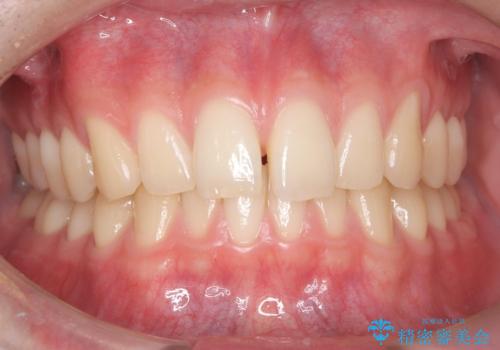

【ワイヤー矯正】すきっ歯を治したい

- 主訴:上の前歯のすきっ歯を治したい。

上顎中切歯間の隙間の他にもフロスが抵抗なく入るスペースが上顎は数か所ありました。スペースを閉じ下顎の歯列弓との調和をとるためIPRを行いました。